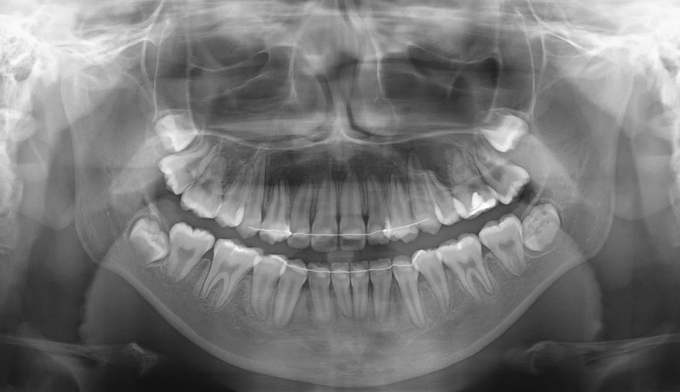

좁은 위턱을 확장하여 치아를 배열할 공간을 만들어주었고, 이 공간을 이용해 치아를 배열합니다.

아래턱의 과성장이 심해지고 있어서 절충치료로 아래치열을 배열해줍니다.

이미 송곳니와 작은어금니의 위치가 꽤 많이 바뀐 상태에서 치과에 내원하게 되어 어쩔 수 없이 최종적인 위치를 바꿔서 배열합니다. 씹거나 말하는데는 전혀 문제가 없습니다.

총 치료기간은 26개월 입니다.